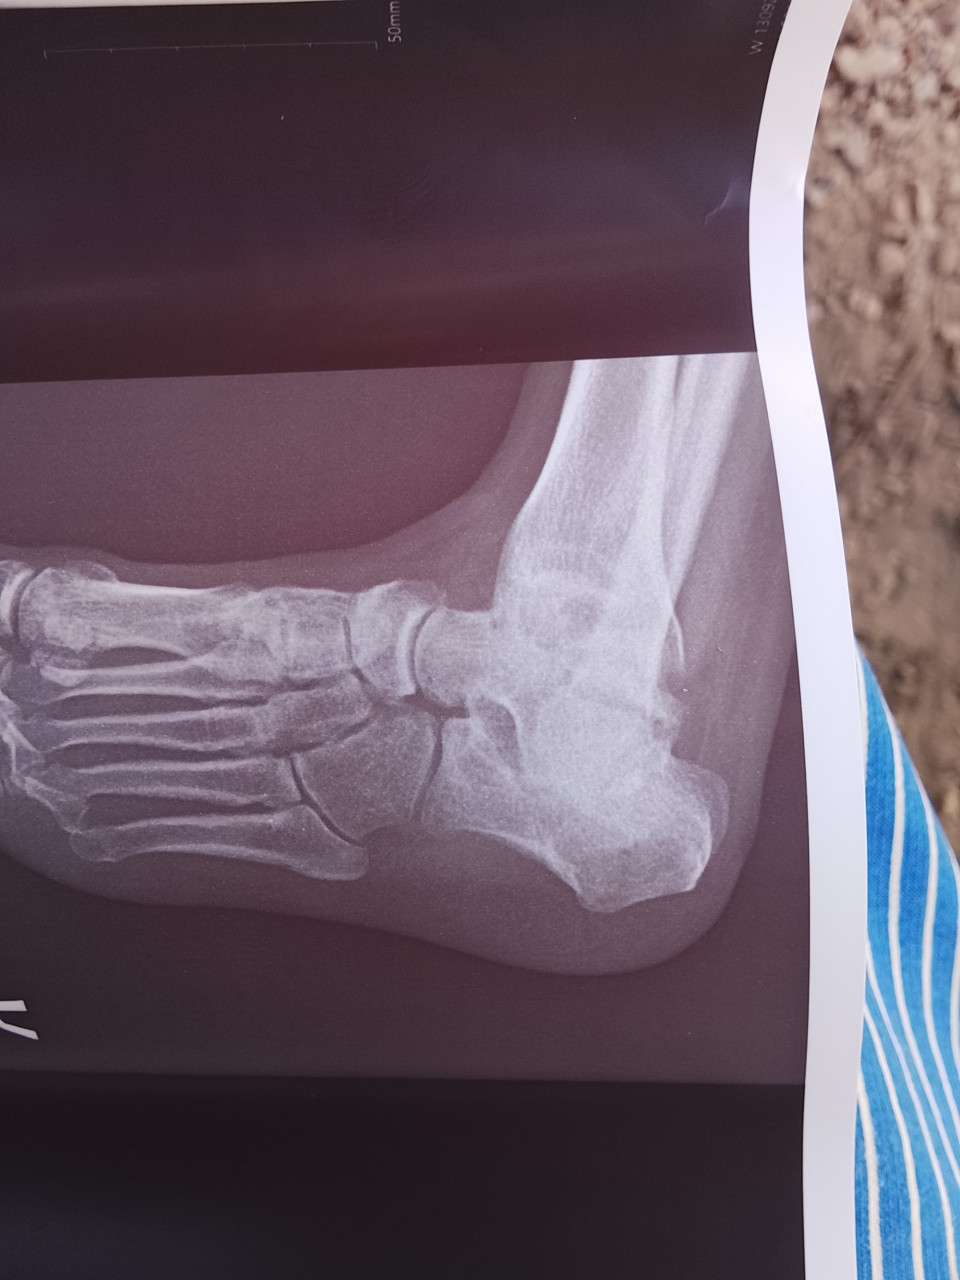

4месяца назад был перелом таранной со смещением сейчас говорят артроз запущенный подскажите пожалуйста чего именно

Здравствуйте. По рентгену видно, что суставная щель в области таранно-пяточного и таранно-ладьевидного суставов сужена, контуры костей неровные  это признаки посттравматического артроза, вероятно из-за нарушенного восстановления после перелома таранной кости.

Здравствуйте. Речь о подтаранном и таранно-ладьевидном артрозе. Это осложнение типично после переломов таранной кости со смещением. Рекомендуется консультация ортопеда для обсуждения вариантов лечения  от физиотерапии и ортезирования до оперативного вмешательства при выраженной боли.